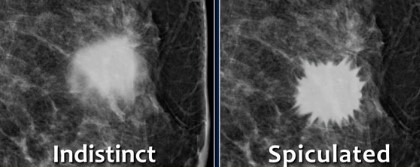

Abnormalitas pada Mamografi

Setiap area yang mencurigakan dan tidak terlihat seperti jaringan payudara normal misalnya

- Area opacity yang signifikan, peningkatan kepadatan

- Titik / bintik putih kecil dalam kelompok yang dikenal sebagai sertifikasi mikro

- Marjin massa yang tidak teratur, tidak jelas, dan bercabang

- Hilangnya arsitektur payudara normal.

Massa yang mencurigakan akan lebih terlihat baik pada payudara yang kurang padat daripada payudara yang lebih padat